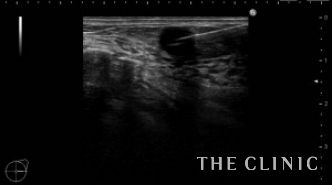

この方は2年前に他院にてバッグ抜去+脂肪注入(片側400㏄)を受けられています。その際、被膜の中に脂肪が入ってしまい血流が途絶えたために脂肪壊死となりしこりになってしまったようです。一番大きい物で6㎝の充実性のしこりがありました。(左の画像)その他にもオイル状の小さいしこりがいくつかあり、皮下にあるものは針で刺してオイルを吸引除去しました。(右の画像)

6㎝のしこりの被膜は肥厚し、内部は充実性のしこり(脂肪壊死)とオイルの両方を認めます。肥厚した被膜を破りチューメセント(麻酔)を注入して、脂肪壊死を崩すためベイザーリポを使用します。

脂肪が崩れた後は吸引を行い、しこりは消失しました。右側は吸引除去した壊死脂肪です。